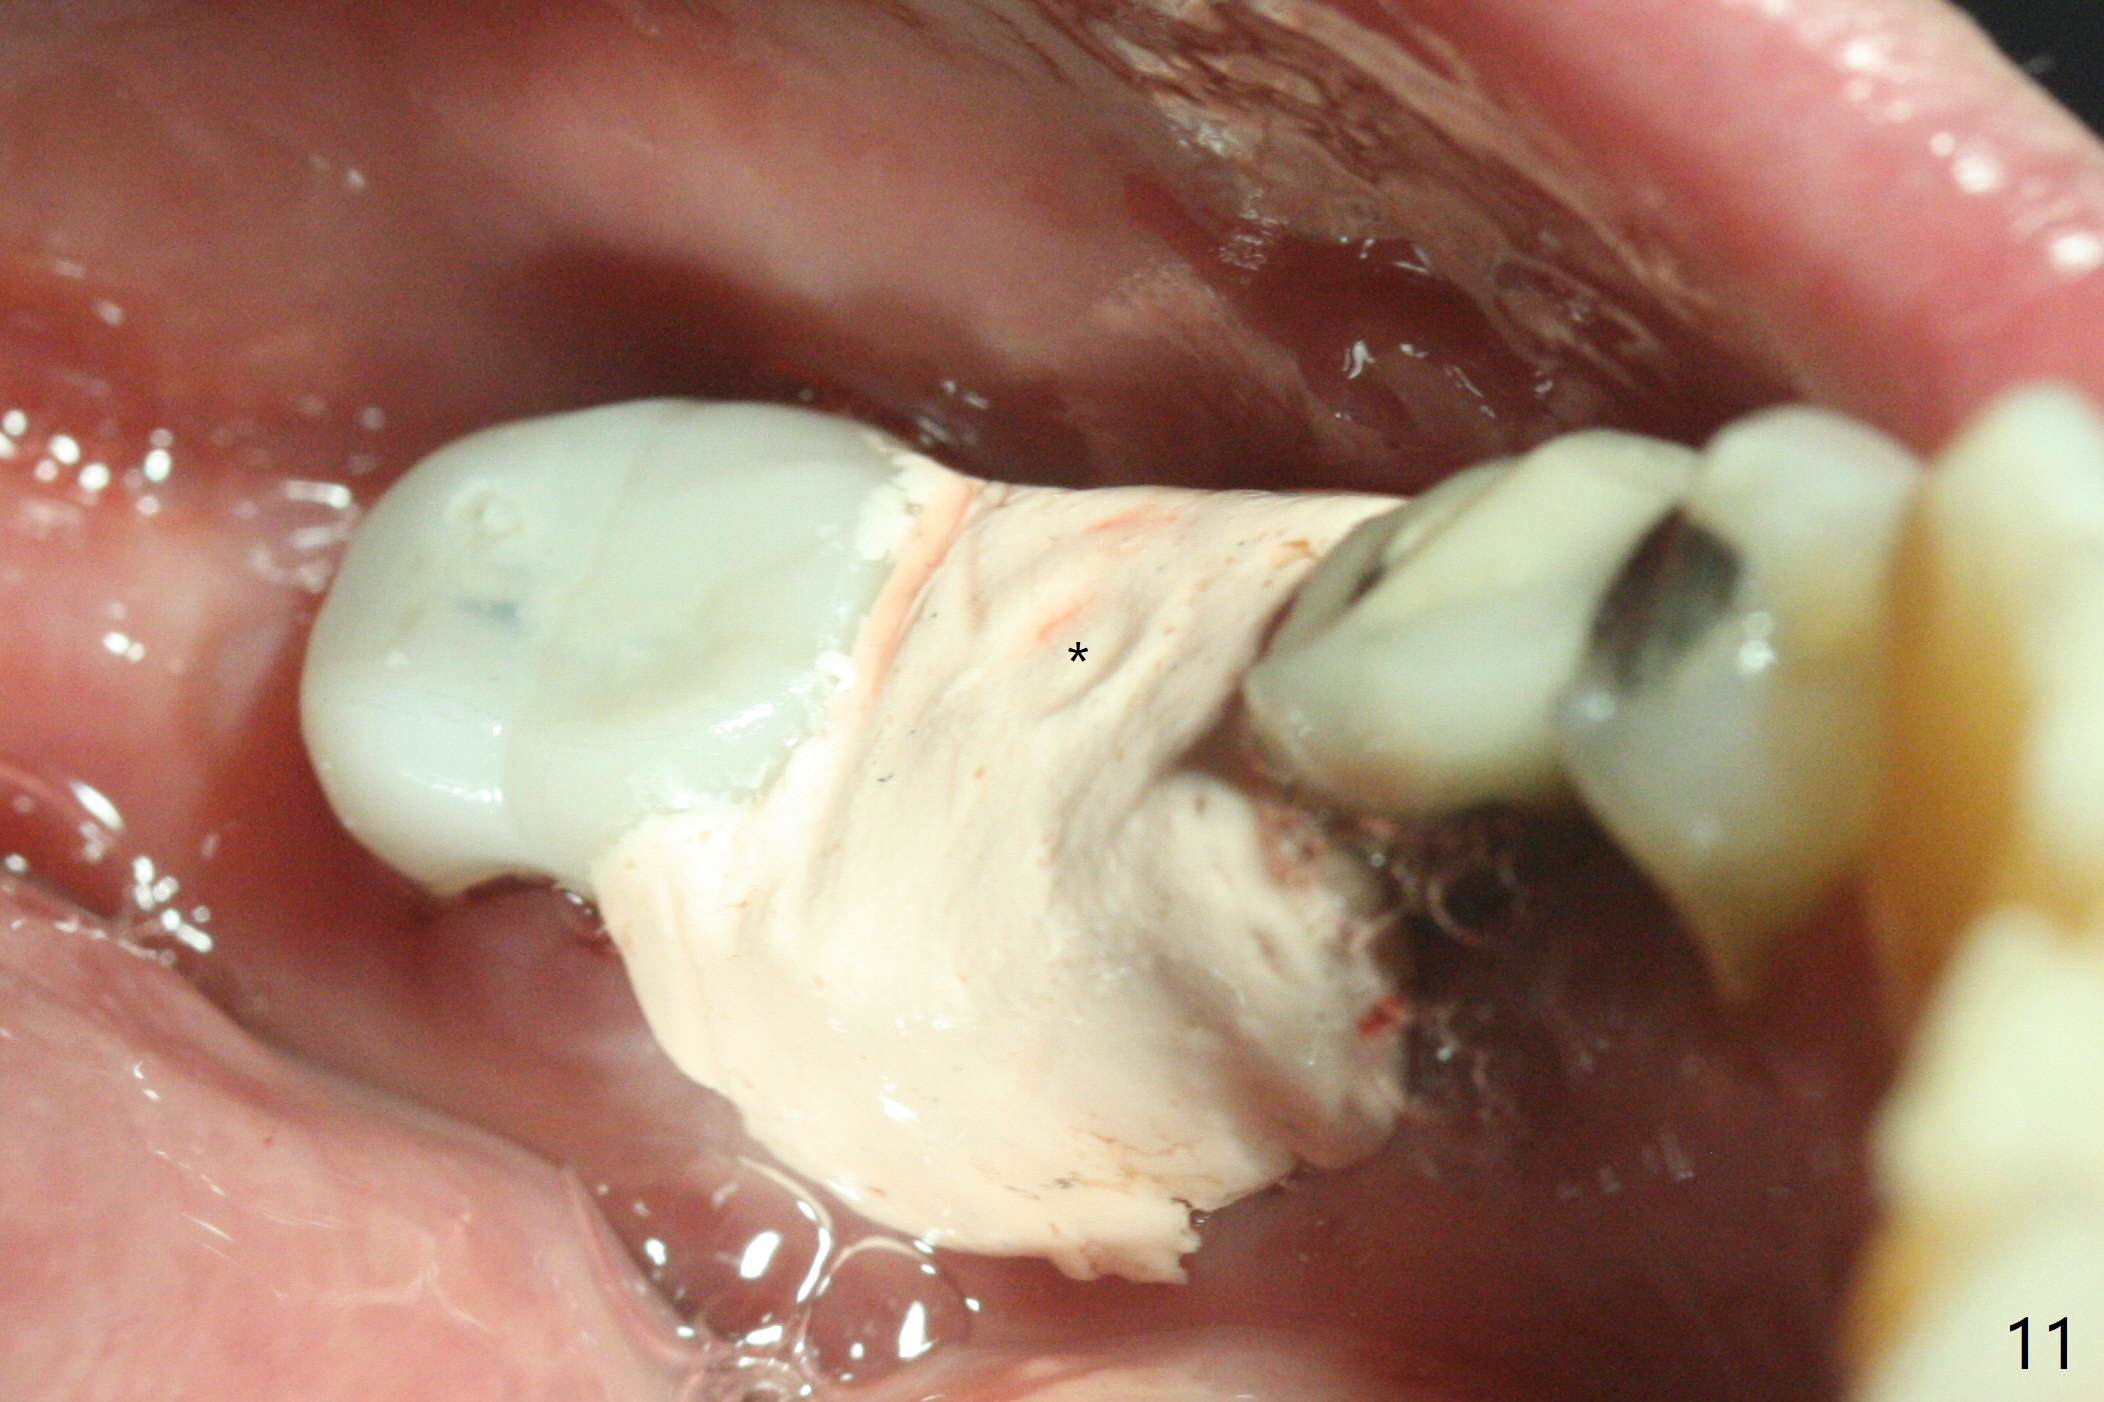

When the patient returns 4 months post implant removal and bone graft, the ridge at #19 is concave with a small hole which communicates with the underlying bone (Fig.1 <). The low density bone in the middle of the socket is ignored (Fig.2 *, 3 S (soft)). With under drilling, primary stability of tissue-level taps is lower. A bone-level dummy implant is placed with low torque (Fig.4). After removal of granulation tissue distal to the osteotomy, a larger implant is inserted with ~15 Ncm; mixture of autogenous bone and allograft is packed (Fig.5 *). The latter is covered by 12x12 mm BioXclude and sutured with 4/0 Chromic Gut tension free. 植牙后6.5月牙槽嵴饱满,角化龈宽(图六(刚开始浸润麻醉))。术后6.5月切开证实植体上面没有骨质覆盖(如图七:*),第一螺纹可能暴露(>)。由于骨质吸收,大号基台置入没阻挡,或者困难(图八),第一螺纹暴露(>)需要再次植骨(图九:*)。放置大号基台(6x6(4)毫米)和植骨使萎缩牙槽嵴部分得到修复(图十,与Uncover前(图六)对比)。Uncover时即刻置入修复性基台好处是利用基台牙龈外部分强化牙周敷料固定,基台中央放置一个棉球后,敷料可以插入基台中央进一步增加固位(图十一(舌侧观):*)。